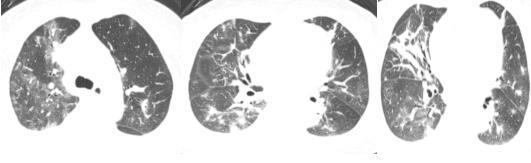

67岁的李女士(化名)长期受高血压、脑梗死后遗症困扰,需要持续气管切开维持呼吸。更严重的是,她的气管内出现了肉芽样新生物,反复阻塞气道,且李女士自身咯痰能力差,导致肺部感染反复且加重。

“这类患者往往陷入‘感染-治疗-再感染’的恶性循环。”柯佳介绍,“我们采用‘中药清热化痰、益气健脾+气道介入+呼吸康复’的综合方案,通过支气管镜下灌洗清除分泌物,氩气刀联合冷冻消融,彻底清除气道新生物,且创口愈合时间缩短50%,术后患者恢复通气。”

经过26天的精心治疗,李女士终于成功封管,呼吸功能得到显著改善,现已转入康复科进行神经功能训练。

切除的气管内新生物组织